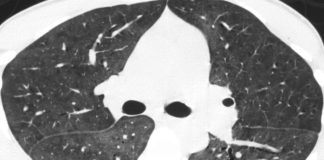

“Ecco l’intelligenza artificiale che diagnostica la polmonite da COVID-19 in 20...

L'emergenza coronavirus in Italia non sembra ancora aver superato la fase di crescita esponenziale, con il numero di contagi e di decessi che aumenta...